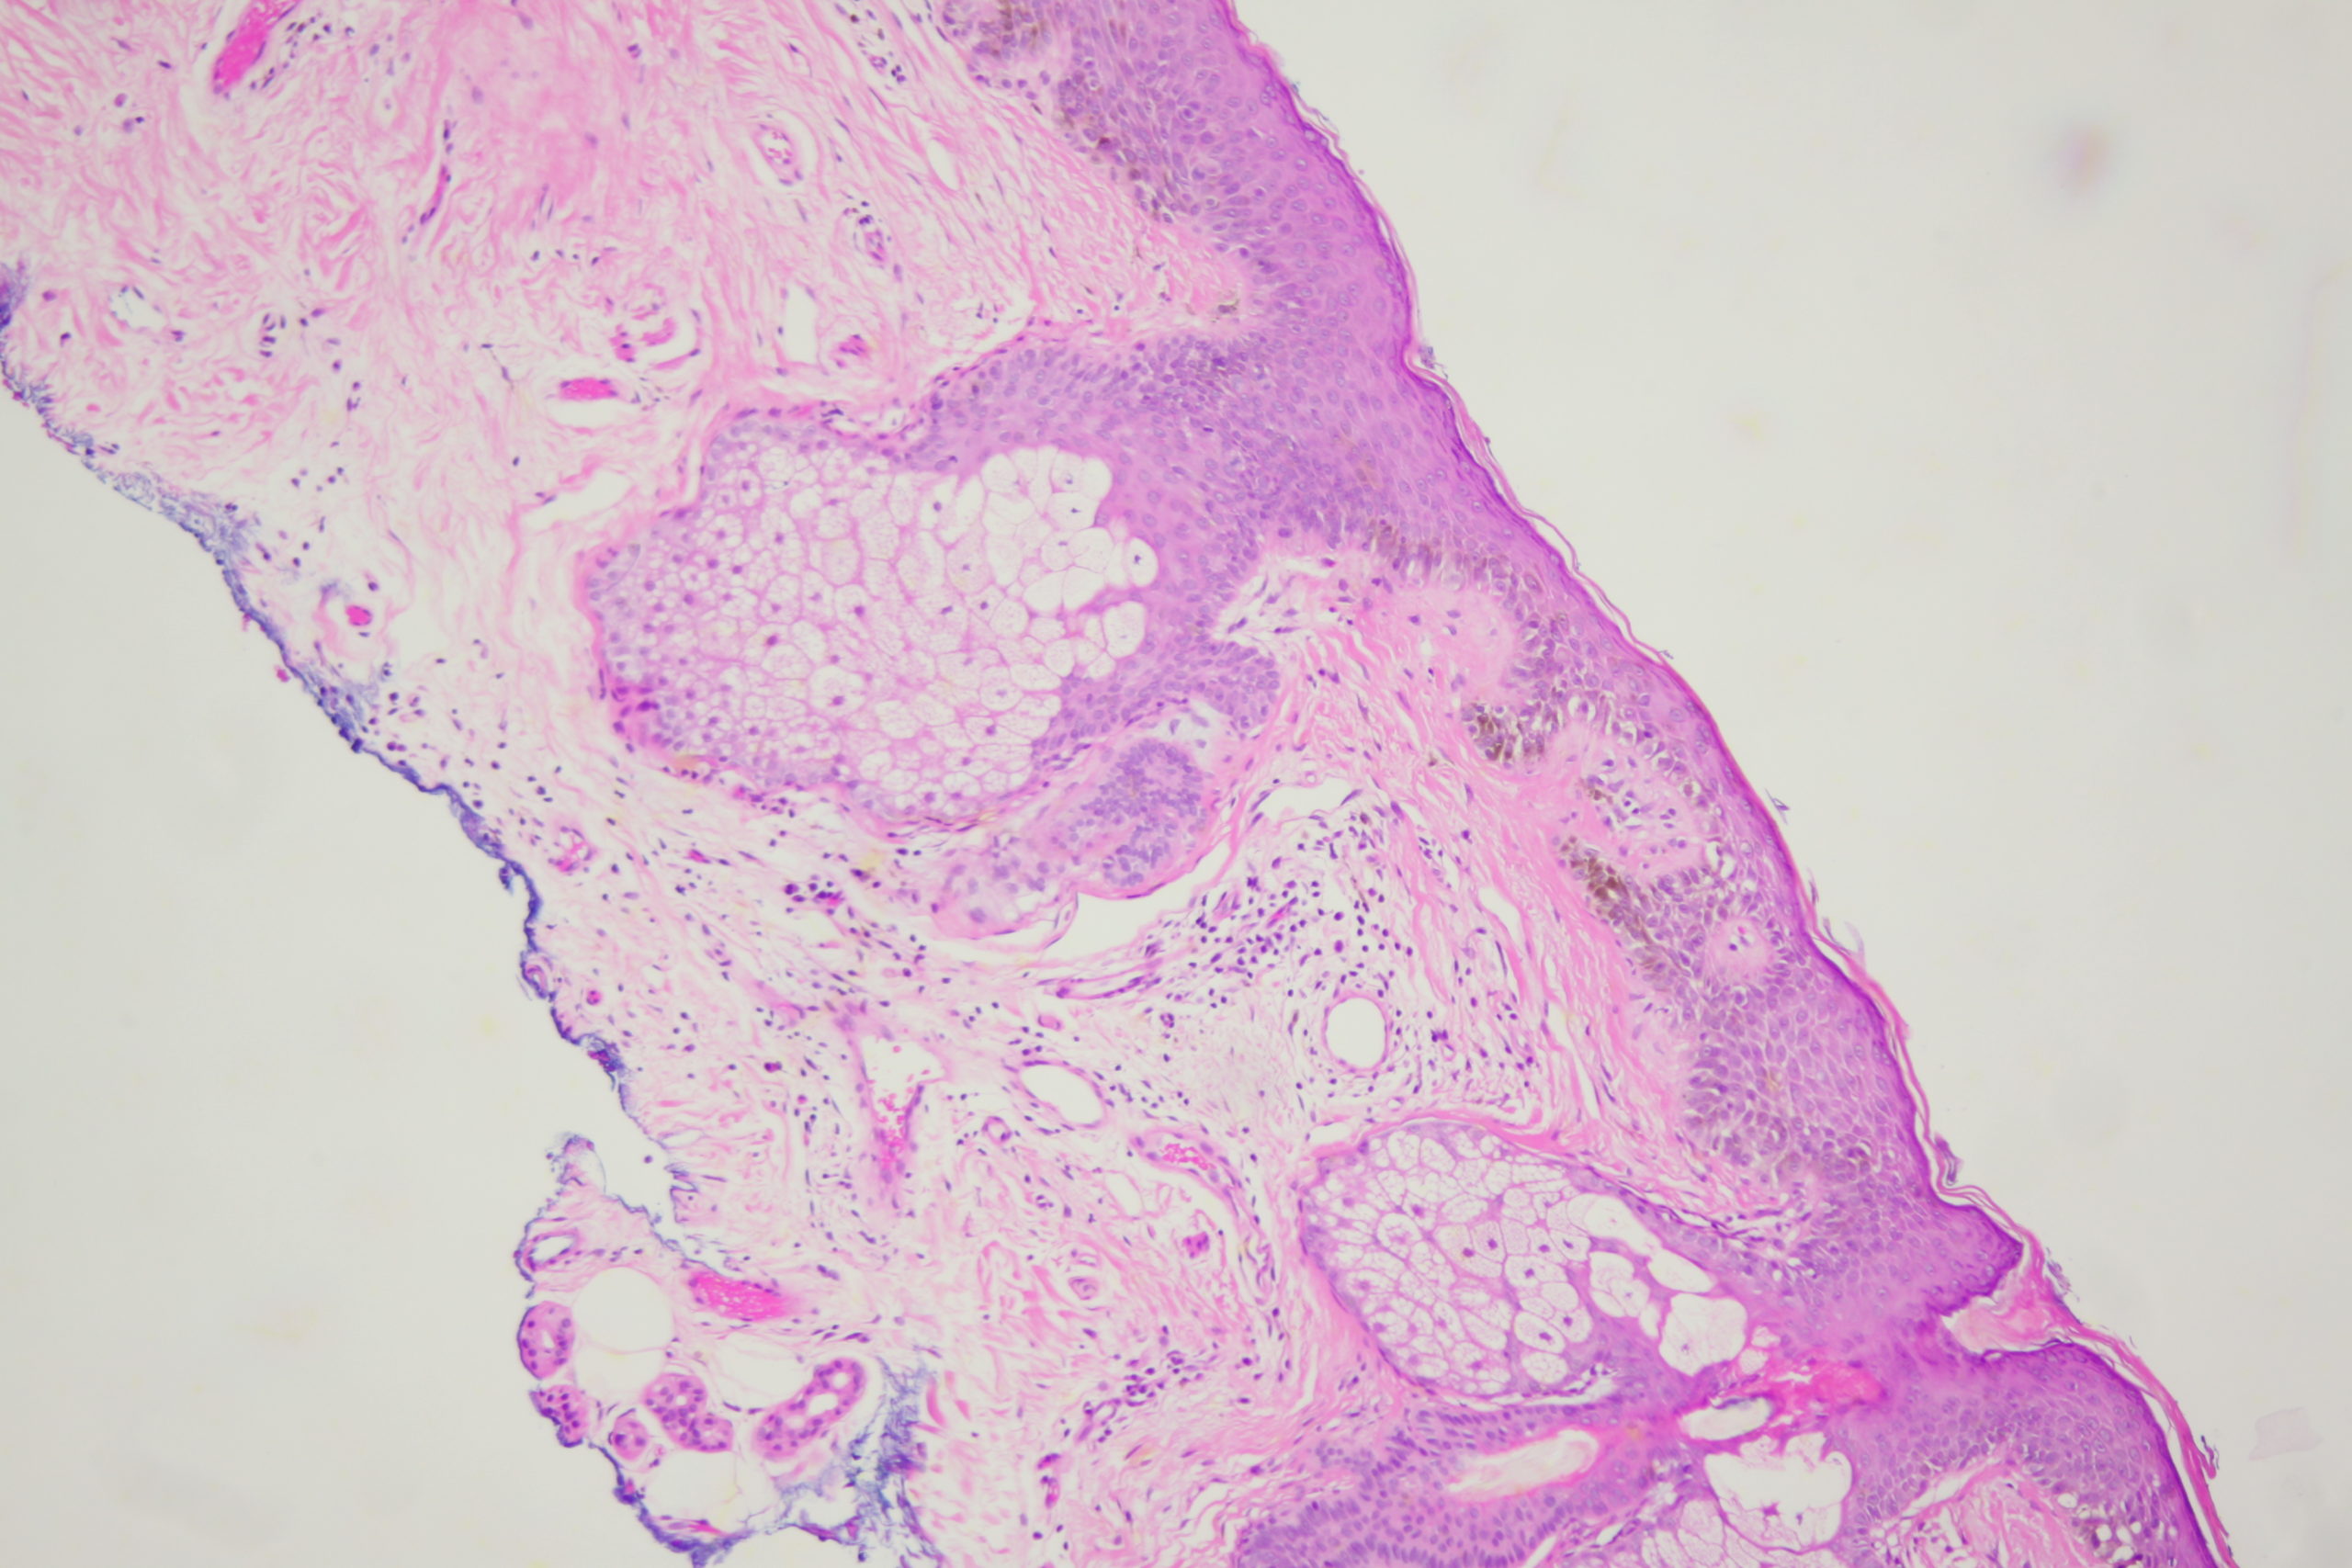

Site: Cheek

Diagnosis: Lentigo Maligna

A pigmented lesion on the cheek that has slowly been increasing in size over several years. Male aged 65. Smooth surface.

Dermatoscopy shows pigment dots and pigment around follicles as grey circles. PRAME and Sox 10 showed atypical melanocytes along the DEJ extending into and down follicles with localised upward pagetoid spread. Early Lentigo maligna / Superficial intraepidermal melanoma.